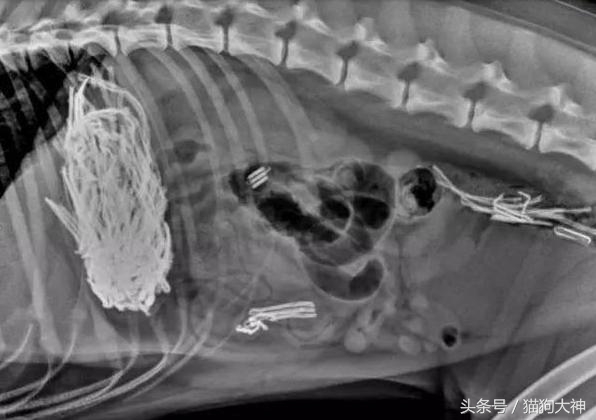

这只大丹犬曾经震惊过整个宠物医疗界。某天,主人发现狗狗精神不振,于是连忙送去了医院。

这是X光片的情况,狗狗的胃里塞满了不知道是什么的东西,反正消化不了并且堵住了肠胃。

手术结束后,医生将从狗狗胃里取出的43只袜子摆在了主人面前,主人简直惊呆,他没想到,家里丢失的那些袜子竟然全部被狗吞了。